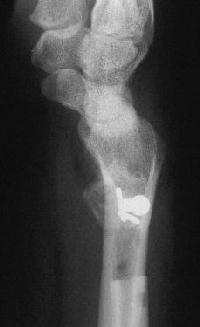

Case 3. Adult bilateral congenital Madelung's deformity with pain and extensor tendinitis, treated with the Sauve Kapandji (Lauenstein) procedure: segmental distal ulnar ostectomy and distal radioulnar joint fusion.

And the left side, preop:

And postop: Here, an inadequate ulnar gap led to heterotopic bone formation which almost resulted in a pseudarthrosis.